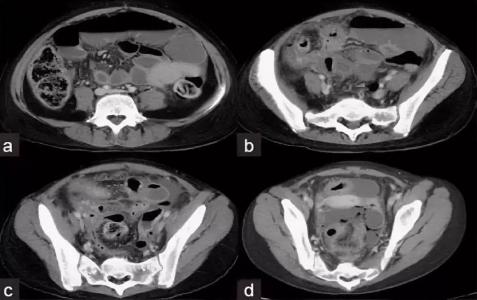

Компьютерная томография органов малого таза нужна для диагностики патологий мочеполовой системы. Также данное исследование необходимо для контроля динамики терапии, оценки состояния мочеполовой системы перед выполнением хирургического вмешательства и после него. Зачастую при томографии необходимо контрастирование, при котором препарат вводится внутривенно. Применяют смесь с содержанием йода, в результате рентгеновские лучи не проникают через контраст. Всевозможные опухоли и болезни сосудов гораздо легче диагностировать с применением контрастного вещества, чем при томографии без использования окрашивания. Контраст является безопасным для здоровья человека, противопоказанием является аллергия к йоду.